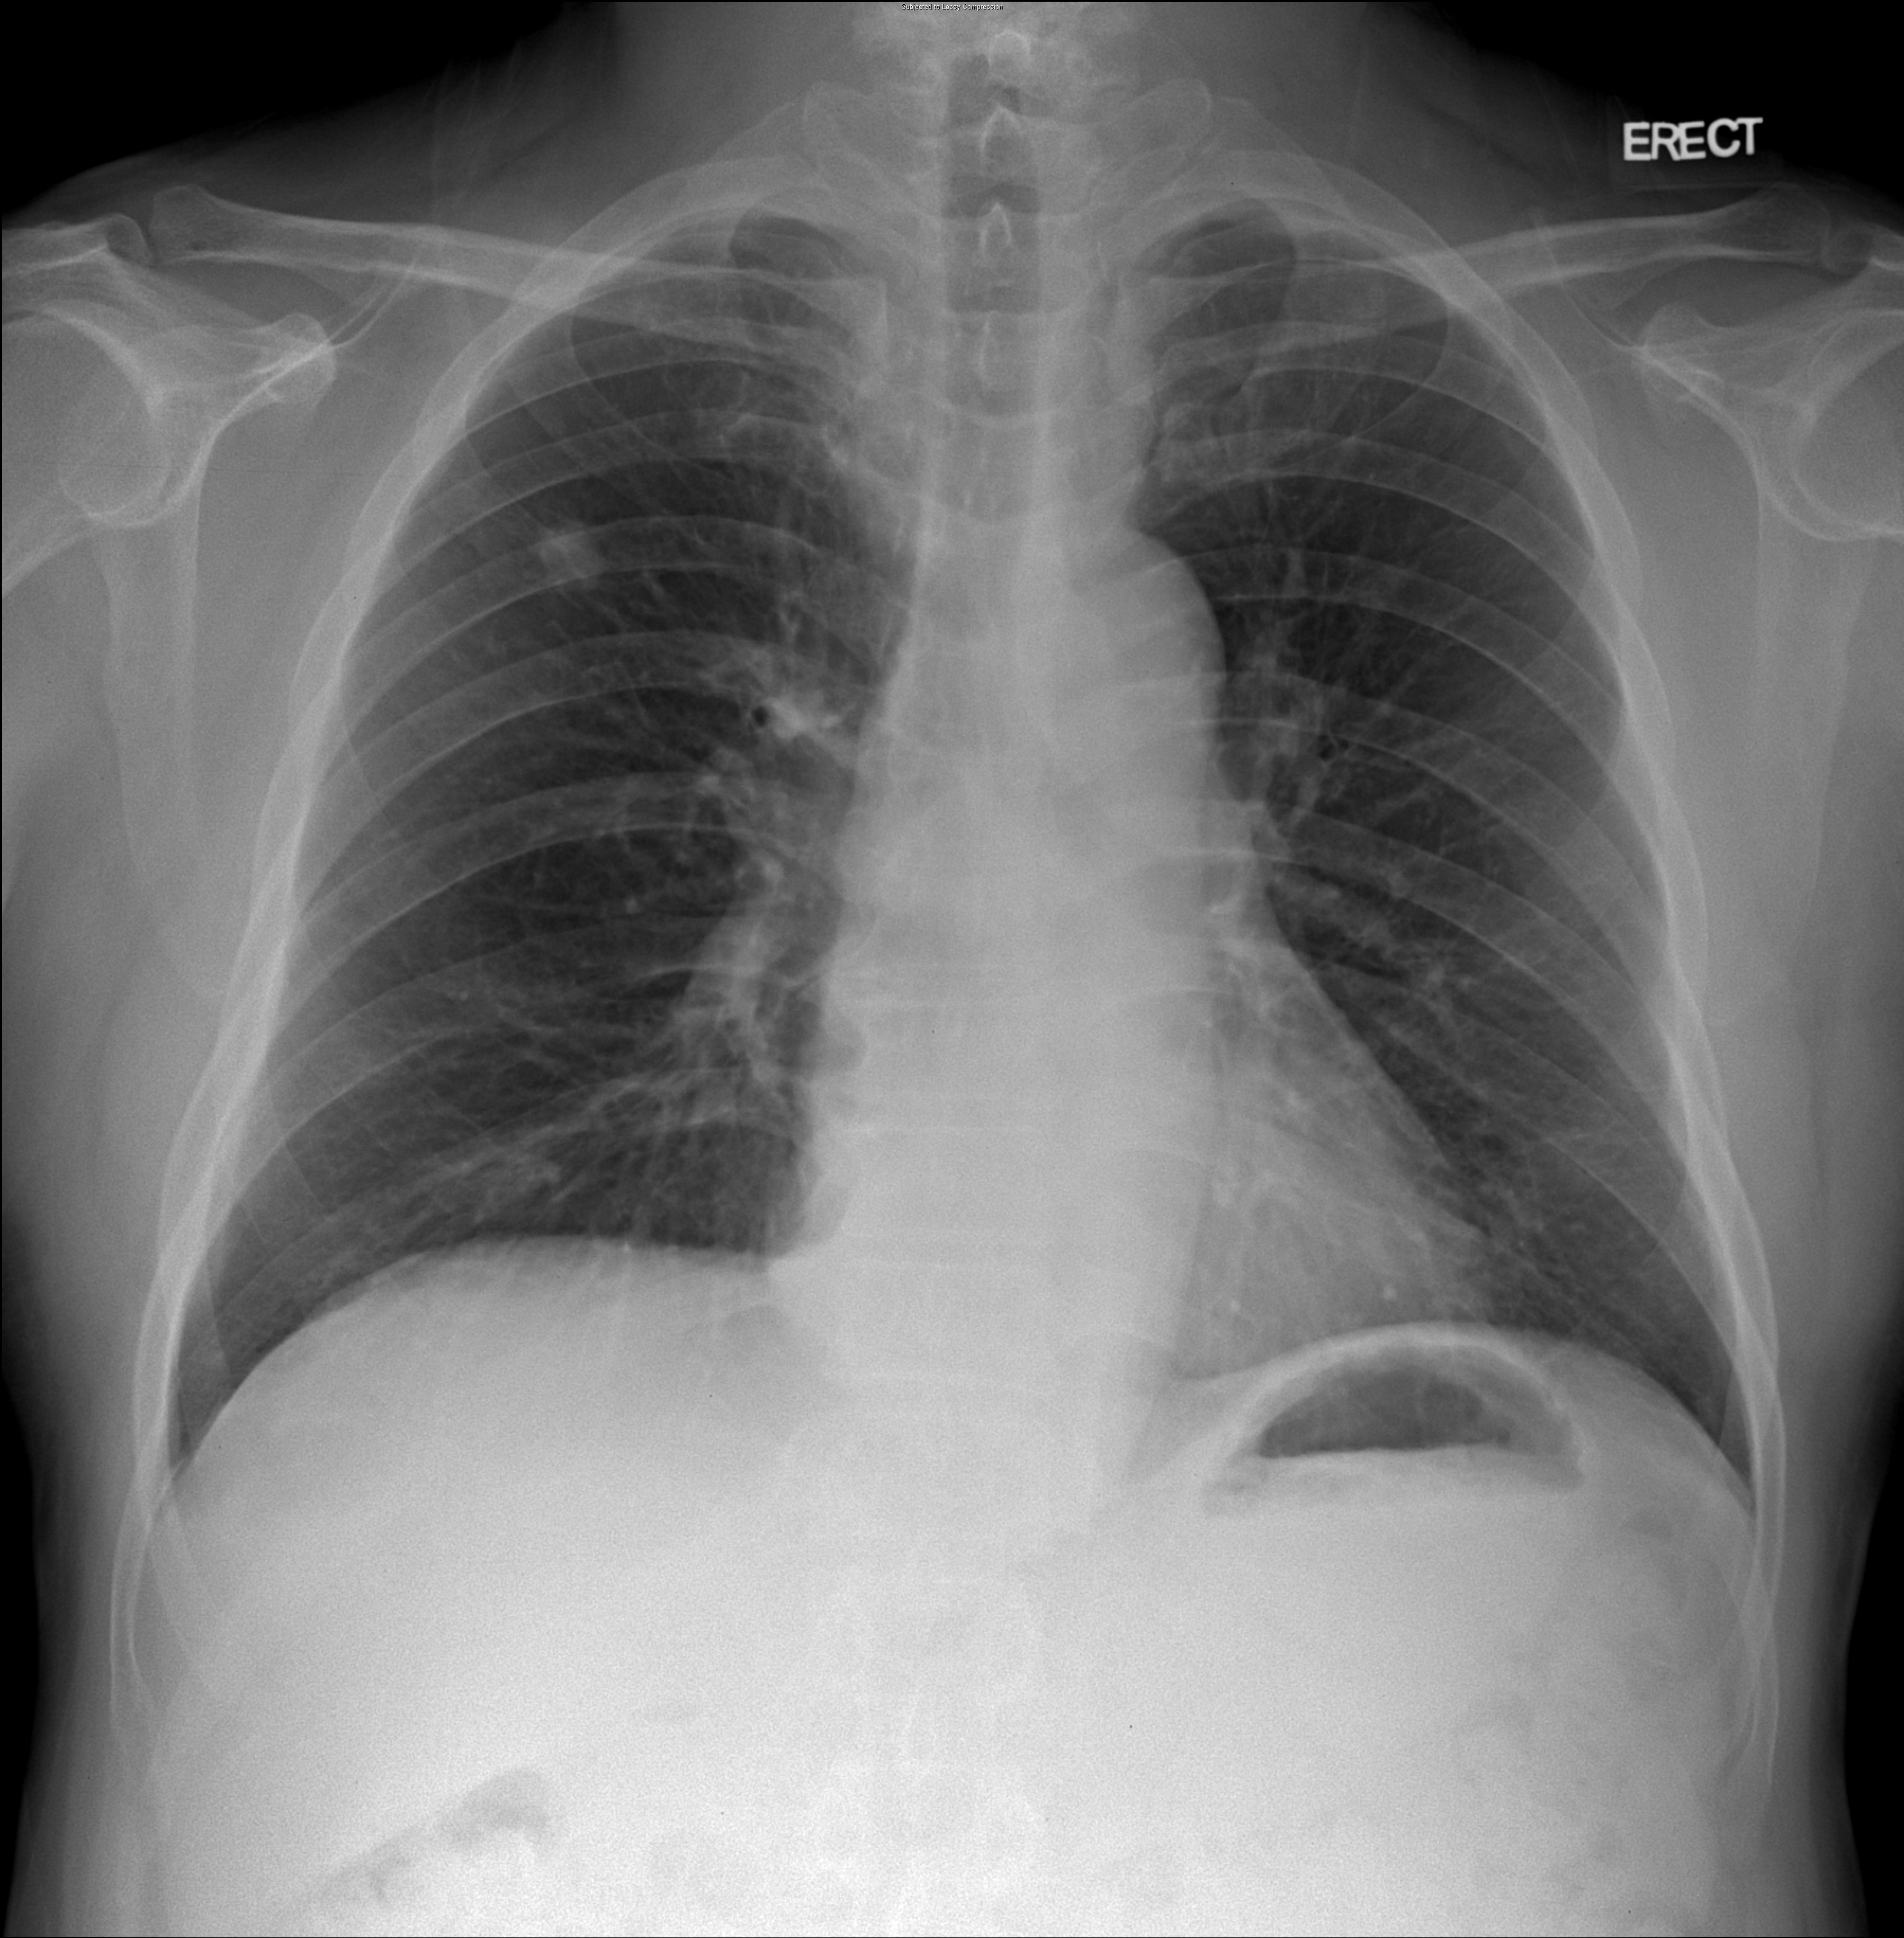

69¼¼ ³²È¯ DM,HTN °ú°Å·Â ÀÖ´ø ȯÀÚ·Î ³»¿ø 10³âÀüºÎÅÍÀÇ right pleural chest pain À» ÁÖ¼Ò·Î ³»¿øÇÑ È¯ÀÚÀÇ CxR ¹× Chest CTÀÔ´Ï´Ù.